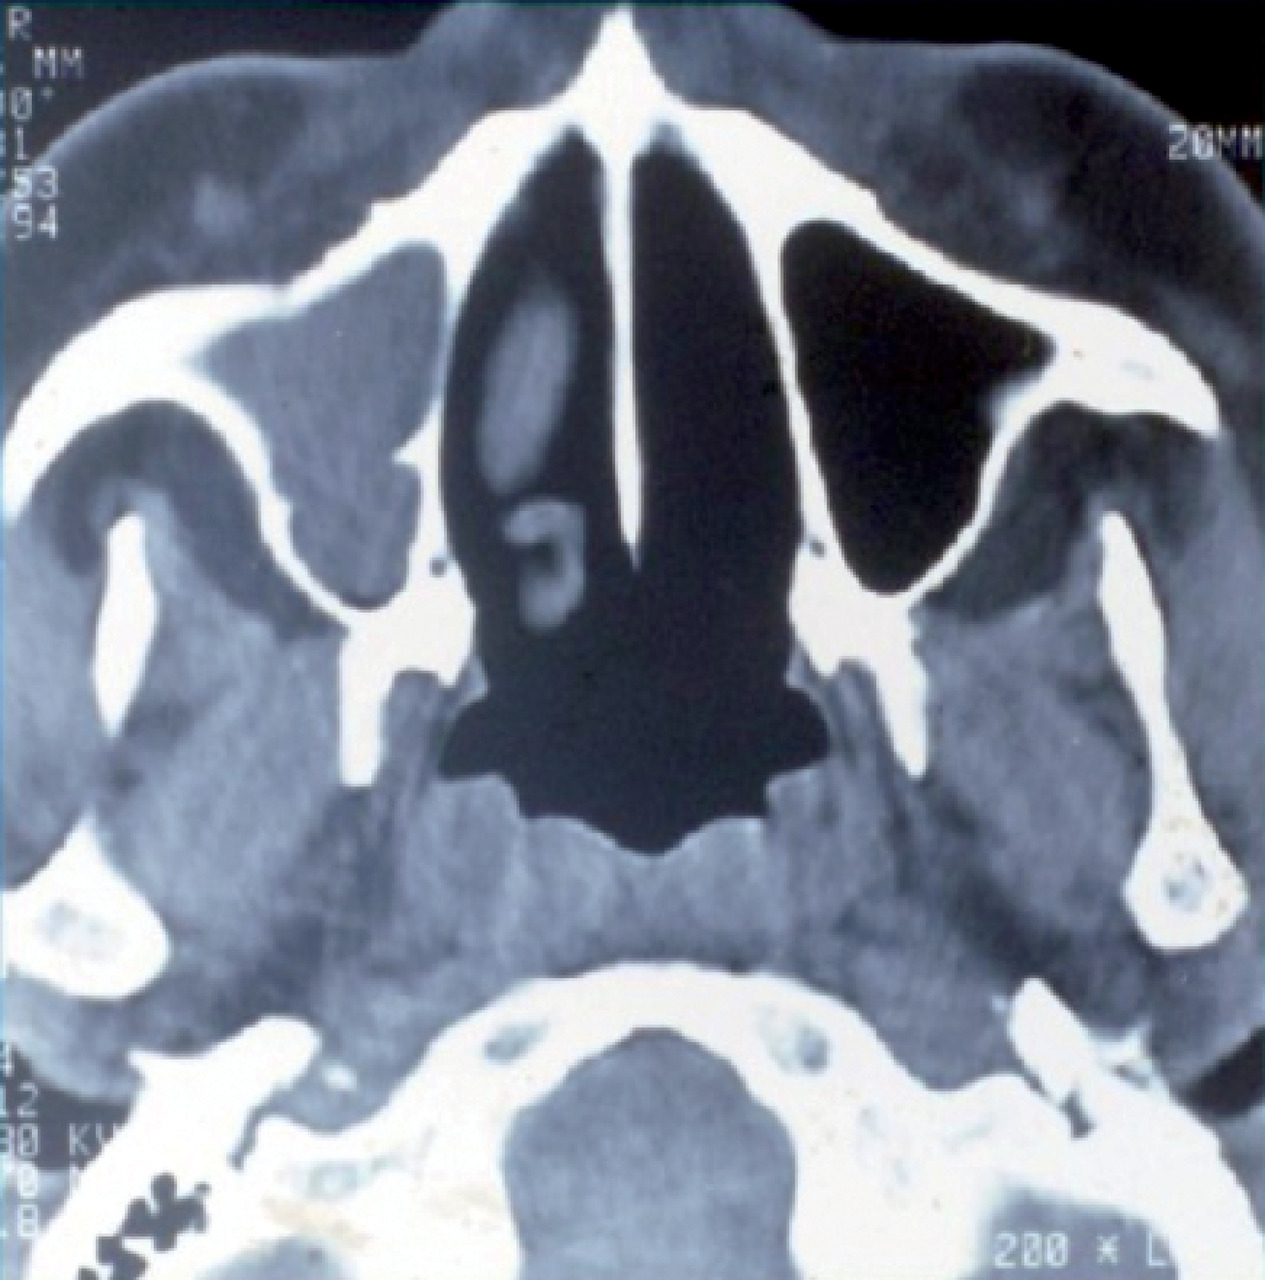

L’atteinte ORL se traduit par des manifestations initialement non spécifiques : rhinorrhée, épistaxis, sinusite ou otite séreuse, pouvant persister durant plusieurs semaines ou mois. La tomodensitométrie montre un comblement des sinus, qui peut évoluer vers une destruction osseuse (fig. 8).

L’atteinte pulmonaire est variable : infiltrats alvéolaires, aspect en verre dépoli, nodules multiples excavés (fig. 9). L’hémorragie alvéolaire, complication majeure mais rare de la granulomatose avec polyangéite, se produit au niveau de la circulation pulmonaire distale entraînant un comblement alvéolaire (fig. 10). Elle se manifeste par une hémoptysie, une dyspnée, une anémie, des opacités diffuses alvéolaires et un liquide hémorragique au lavage bronchoalvéolaire (LBA). Des sténoses trachéo­bronchiques sont possibles.